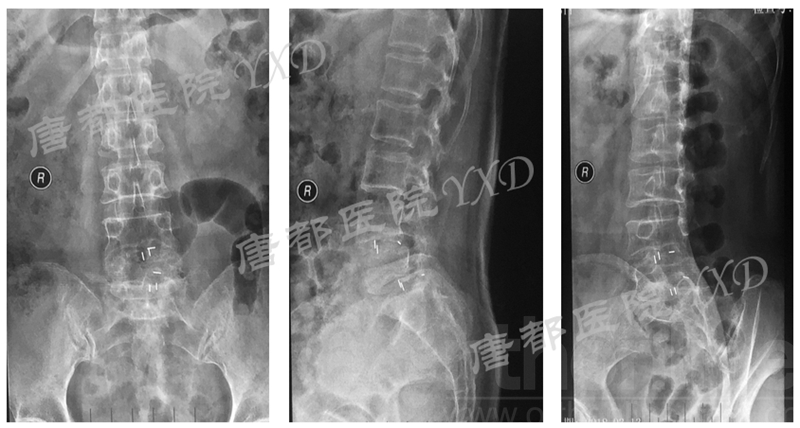

患者60岁,女性。

主诉:腰椎术后左下肢疼痛9月、加重4月。

专科情况:轮椅推入病房;强迫体位;双侧直腿抬高试验、加强试验阴性;左小腿后、外侧及足背、足底皮肤感觉减退;余未见明显异常。VAS评分:左下肢7。

既往8年前因“腰4、5椎弓峡部裂并腰4椎体滑脱症”于外院行腰4~骶1椎板减压椎间植骨融合内固定术,后因椎弓根螺钉断裂于5年前行内固定取出术。

影像学检查:

诊断:腰椎椎间融合术后融合器后移

手术方案:显微镜辅助MI-TLIF腰椎翻修术